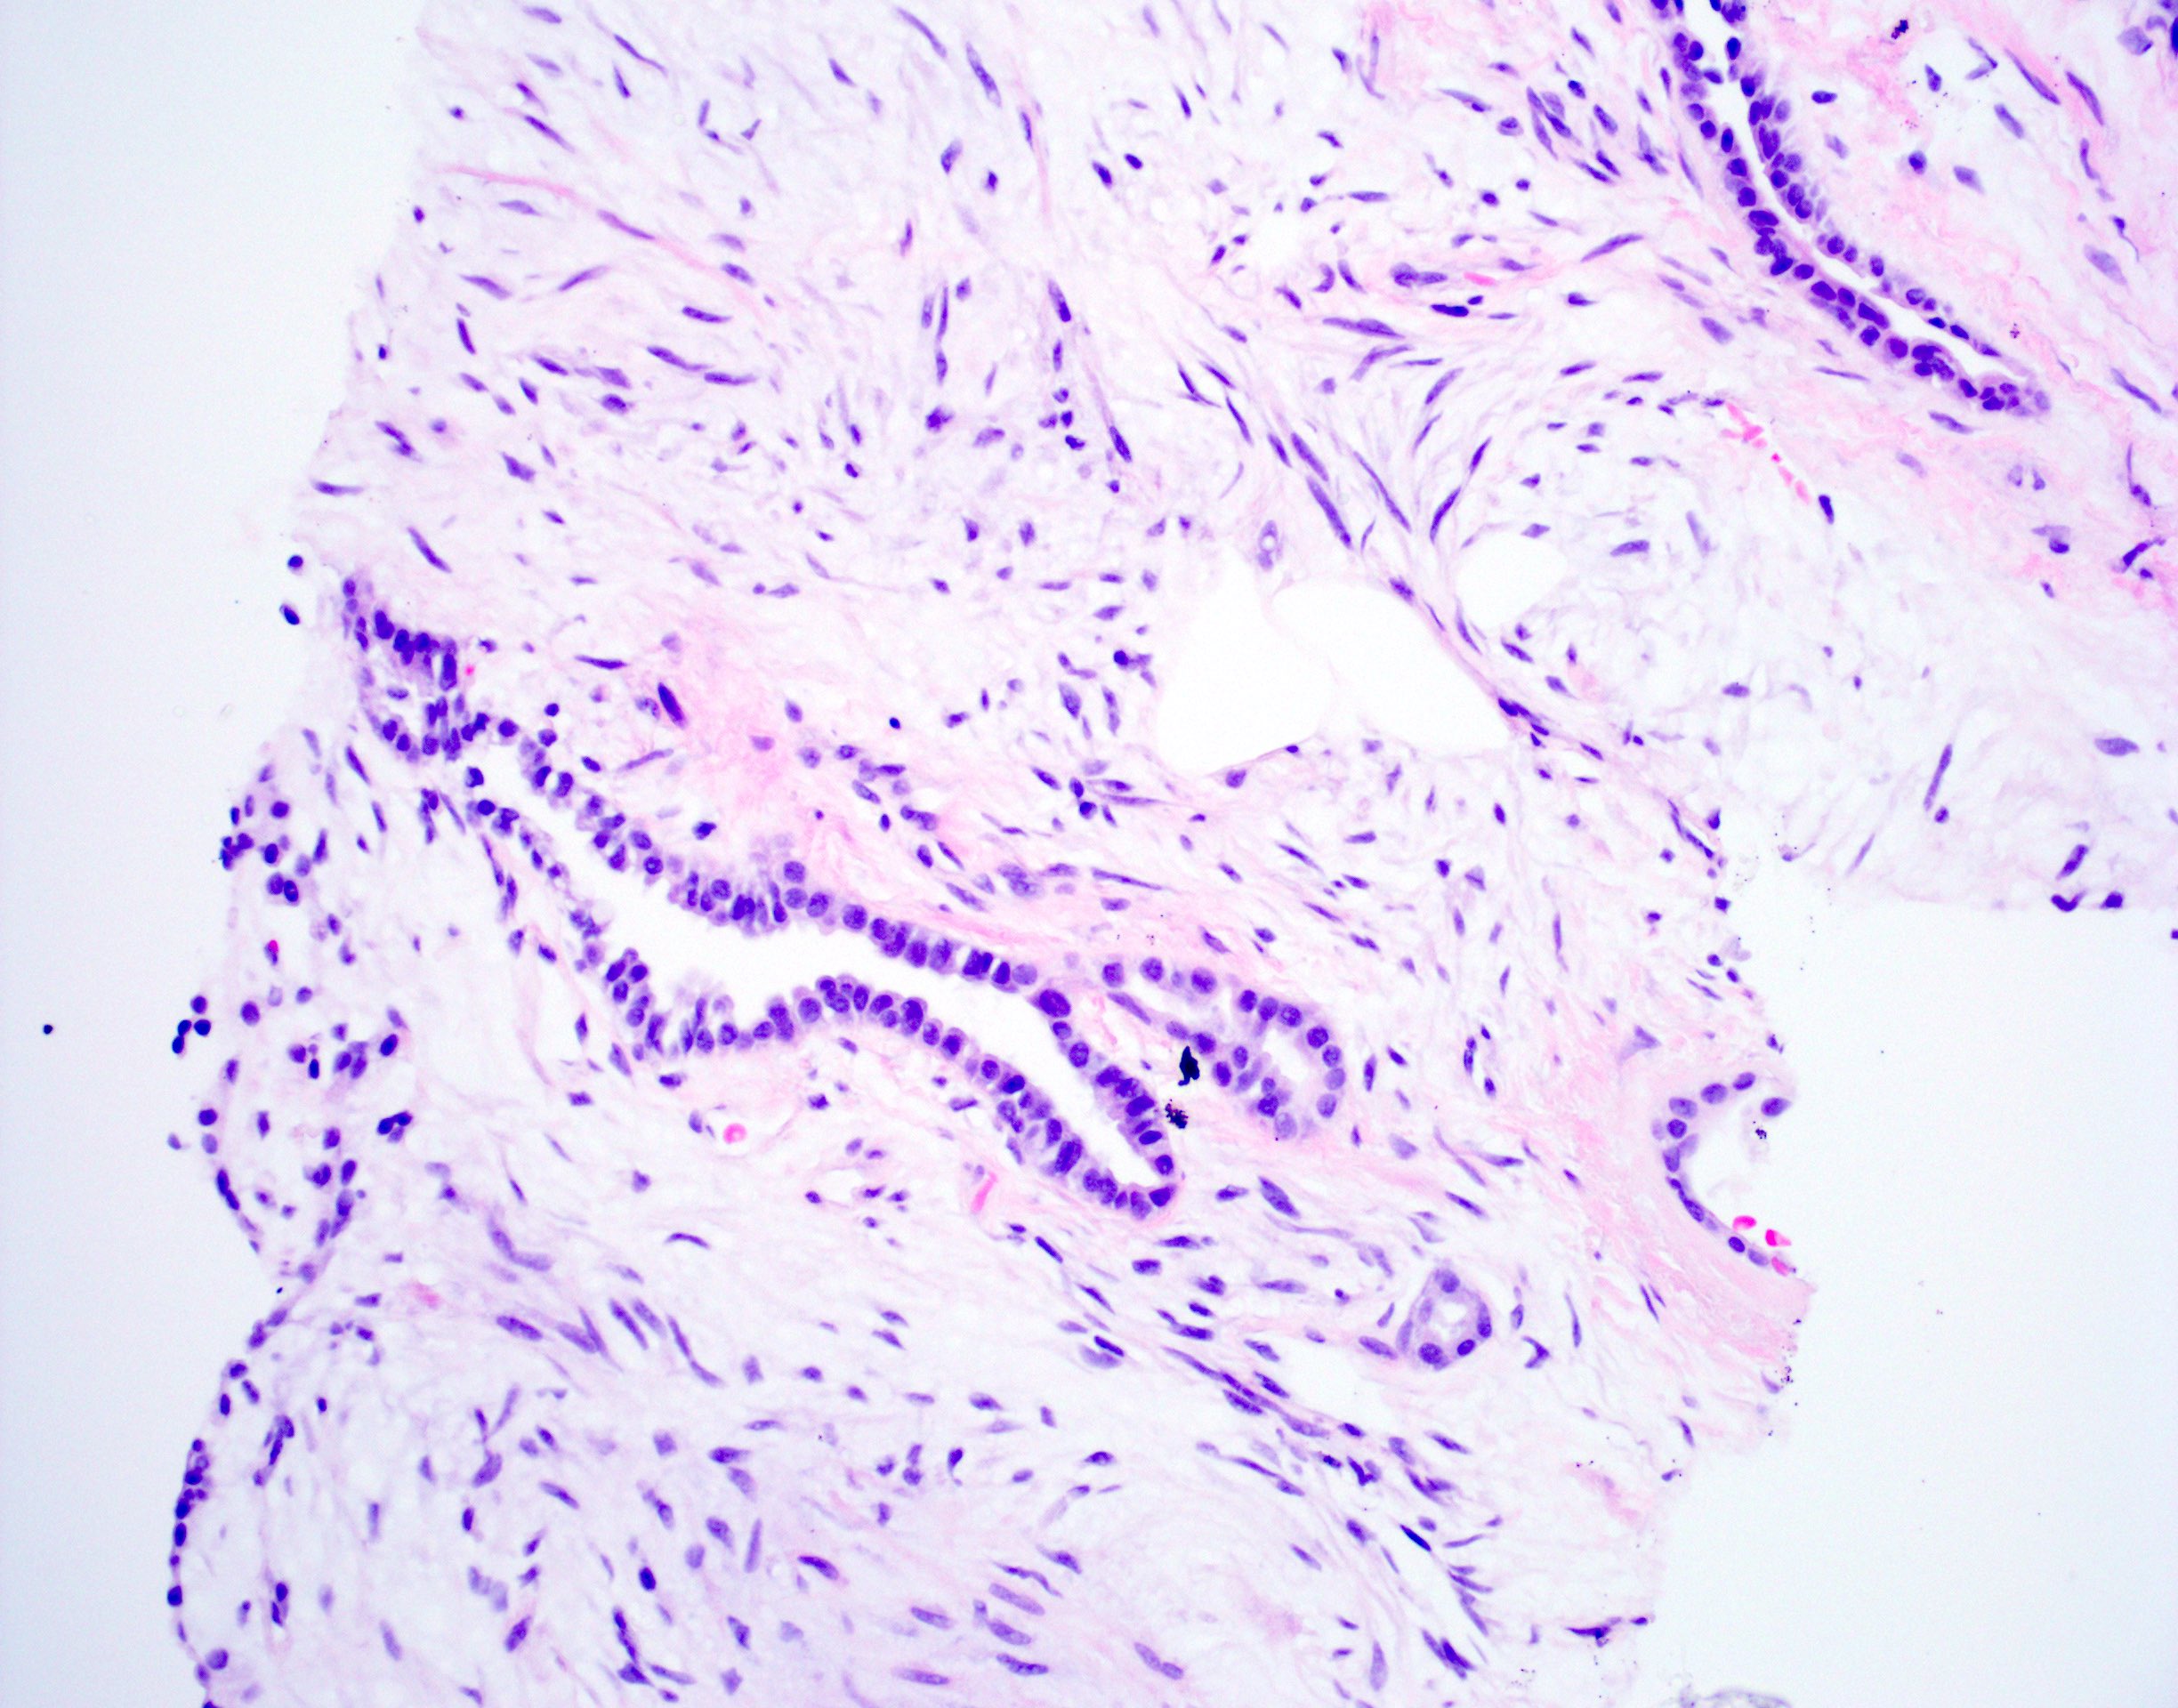

Microscopic (histologic) description

- Composed predominantly of varying degrees of mesenchymal tissue: hyaline cartilage, fat, smooth muscle and bone

- Other connective tissue elements may be present, represented by bland spindle cells, fibrous tissue or myxoid change

- Variably conspicuous, entrapped benign epithelial cells

- Reference: Thorax 1987;42:790

Microscopic (histologic) images

Contributed by Hui-Hua Li, M.D., Ph.D. and Jefree J. Schulte, M.D.

Contributed by @Andrew_Fltv on Twitter